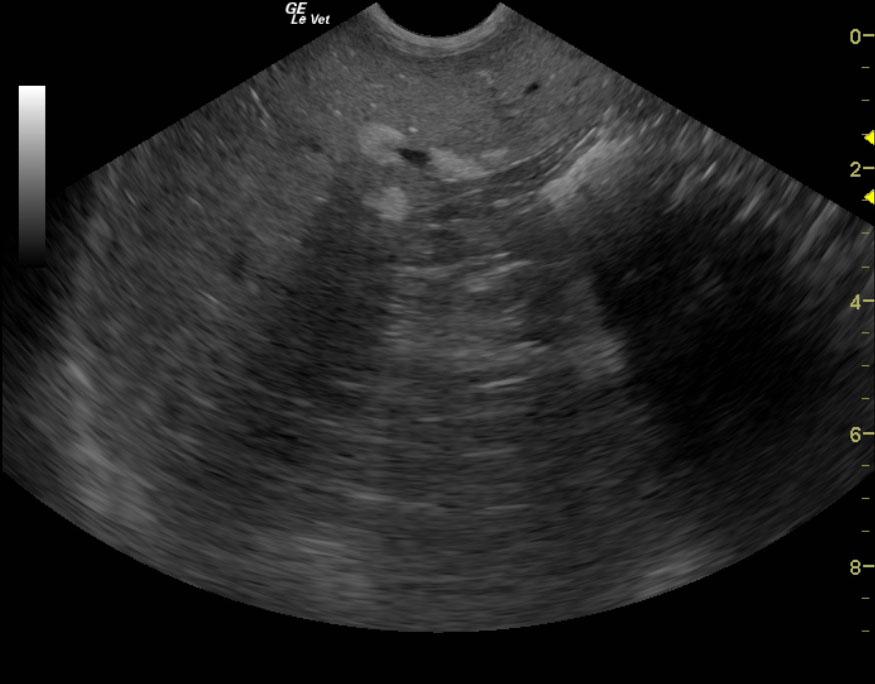

A 12 year old FS Standard Poodle on hypoallergenic diet was presented for a growth on the lip, tachypnea, polyuria/polydipsia, recent trouble managing stairs, and restlessness. On physical examination, the dog had a swollen left lateral stifle, a 1/2 cm black pedunculated mass on the lip, and a stiff hindquarter was evident. Cytology from the lip mass was consistent with a basal cell tumor. On urinalysis, the urine had a cloudy and yellow appearance, the pH and specific gravity were normal, there was a 3+ proteinuria, and a few amorphous urate crystals. Urine culture yielded no growth. Abnormalities on CBC and serum biochemistry were lymphopenia, high ALT and ALP activity, hypercholesterolemia, mild hyperamylasemia, and hyperlipasemia. Total T4 was low, and leptosporosis test was negative.